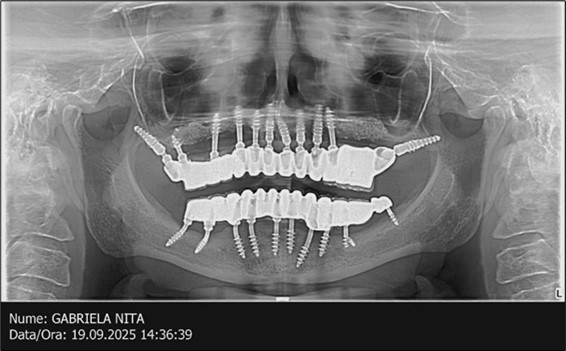

The results of rehabilitation treatment with corticobasal and compressive implants with a polished surface after the failure of two stage implants were highlighted over a period of 3 years and 3 months as being very good (Figure 14, Figure 15), with the patient completing a satisfaction survey in this regard. Certainly, it is necessary to continuemonitoring these results in the long term.

June 2022: Patient presented to our clinic for immediate-loading implant treatment At the time of presentation in 06. 2022, radiologically, advanced peri- implantitis is observed around the implants, with loss of native bone in the affected distal areas (Figure 1)

Figure 1.Panoramic overview picture before rehabilitation 06.2022